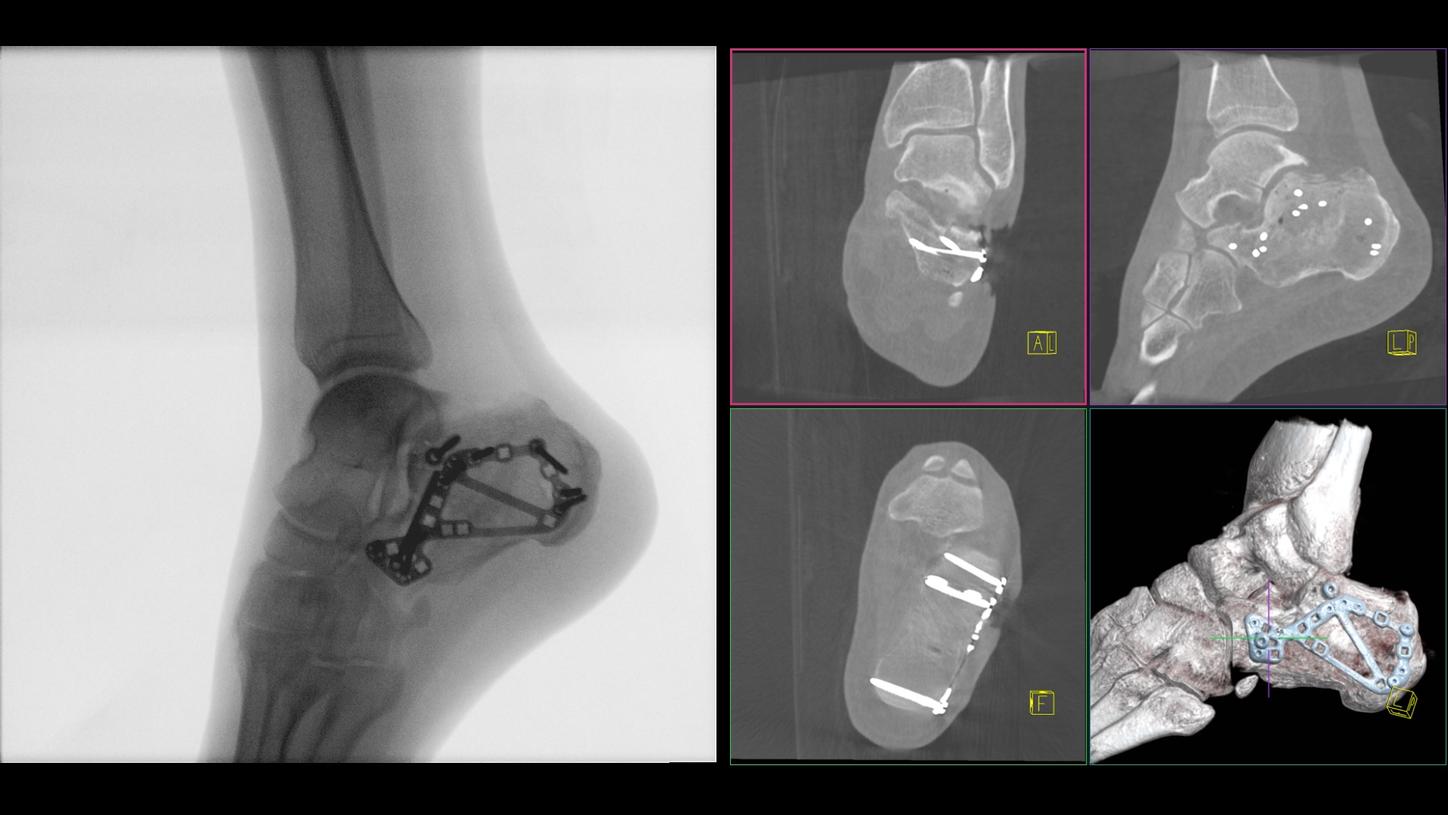

Benefit from precise 2D and 3D visualization of anatomical structures and metallic objects with excellent image quality.

3D volume for image-based registration of navigation markers

25 x 25 x 16 cm (10’’ x 10’’ x 6.3’’); resolution: 800 x 800 x 512 voxels

Screw Scout

Yes2